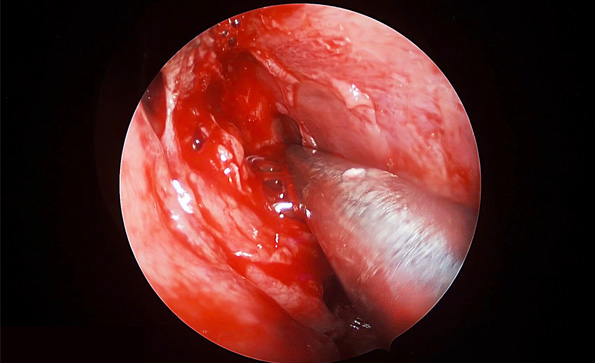

4K超高清內窺鏡攝像系統在腦垂體瘤切除術中的精彩表現